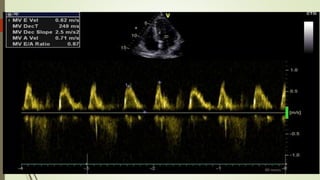

 Spectral Doppler :

• PW: MV (place sample volume at leaflet tips

• CW: Place cursor through the vena contracta of regurgitant jet or MV and TV

leaflet coaptation point.

• TD: Septal and lateral MV annuli, lateral TV annulus

Doppler Examination  ColorDoppler : • MV: Color box should include LA, MV, LV inflow tract. • TV: Color box should include RA, TV, RV, IVS.  Spectral Doppler : • PW: MV (place sample volume at leaflet tips • CW: Place cursor through the vena contracta of regurgitant jet or MV and TV leaflet coaptation point. • TD: Septal and lateral MV annuli, lateral TV annulus Basic use of doppler echo-detection of normal flow and disturbed flow. Quentification of severity of lesion